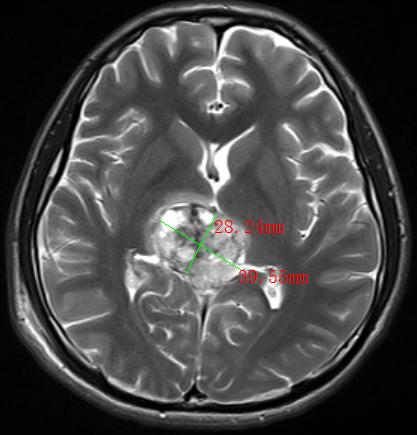

2022年,30多岁的张先生和40岁岁的李先生,均出现神志模糊或不清,并有反复癫痫发作的情况,经过当地医院检查,张先生和李先生分别诊断为松果体肿瘤、间变型星形细胞瘤术后复发并多发种植转移,两人颅内肿瘤直径分别达4.0cm和9.8cm。由于两人颅内肿瘤太大,辗转多家医院求医未果,正当两家人要放弃的时候,听朋友介绍瑞康医院射波刀治疗恶性肿瘤的效果非常不错,两家人怀着试一试的心态来到瑞康医院肿瘤科一区。

松果体区肿瘤MRI影像